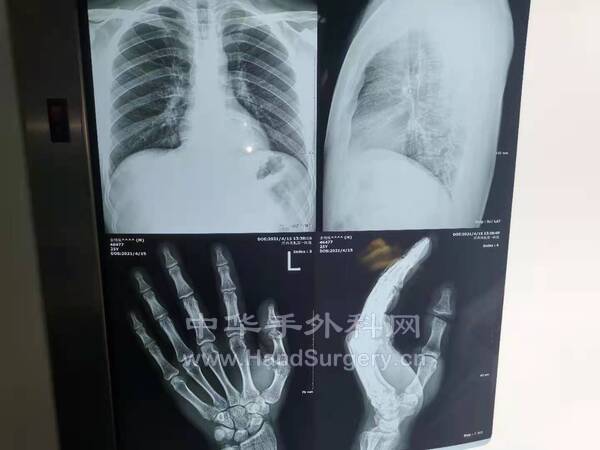

[断指再植] 24岁,拇指离断,掌侧双侧血管神经陈旧性断裂

24岁,拇指离断,1年前掌侧受过伤,肌腱及双侧血管神经束断裂,肌腱重新吻合,血管神经未处理,镜下见瘢痕组织增生,双侧血管神经束陈旧性断裂,断端管壁硬化,术中行血管移植,吻合双侧血管神经,动静比2-4,指间关节做了关节融合,屈伸肌腱做了吻合,考虑到患者比较年轻,日后可能行关节移植,这样效果会好一点,下面就是上照片 (2).jpg (6).jpg (7).jpg (5).jpg (8).jpg (3).jpg